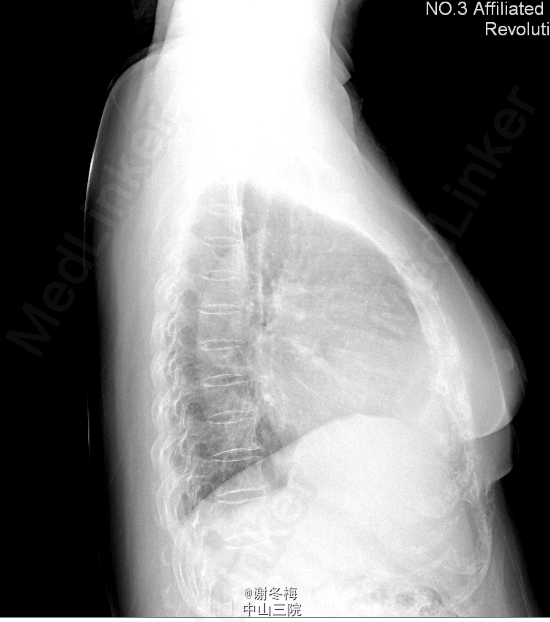

查体:BP108/69mmHg,神清,呼吸平顺,颜面、眼睑无浮肿,皮肤粘膜无苍白,甲状腺Ⅰ度肿大,质软,无触痛,未扪及结节,心率104次/分,律齐,各瓣膜听诊区未闻及明显杂音,双肺呼吸音粗,未闻及干湿性啰音,腹膨隆,腹软,无压痛、反跳痛,双足背动脉搏动可,双下肢无凹陷性浮肿。 辅查:2015-3-16我院行彩超心脏:左房、左室增大(左心房41mm,左室舒张末容积60mm),右房稍大,左室壁普遍性运动减弱,左心功能减低(EF 32%),二尖瓣反流(中重度)。三尖瓣反流(中重度)。主动脉瓣反流(轻度)。肺动脉高压(轻度)。心包积液(微量)。 Holter:1、窦性心律,2、偶发房性早搏,3、频发多源发室性早搏伴成对室性早搏(1836个),4、T波改变。 冠脉CT:1.LM近分叉处狭窄约20%(非钙化斑块);LAD近段钙化斑块,管腔未见狭窄;余冠状动脉CTA未见异常。2.左肺炎症。